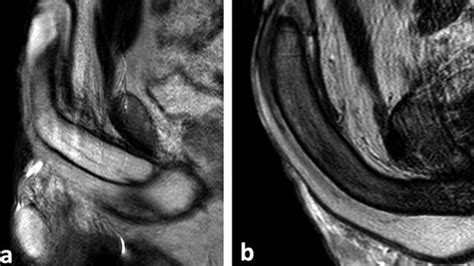

Priapism diagnosis and management: AUA/SMSNA Guideline

What Is Priapism, A Condition in Men, And Can It Occur While Sleeping?

A Simple Guide to Priapism (Painful Erection), Treatment and Related ...

Diagnosing And Managing Priapism: AUA and SMSNA Guideline

Winter Shunt

Winter Procedure

El Ghorab Shunt

Ischemic vs Nonischemic